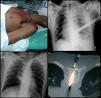

En el primer caso, un varón de 62 años de edad, fue empalado en el tórax izquierdo con un cuchillo de cocina. El cuchillo entró al tórax a nivel del 4.° espacio intercostal y la línea axilar anterior (fig. 1A). El paciente se encontraba hemodinámicamente estable. La radiografía de tórax mostró hemotórax izquierdo y el cuchillo se apreció sobre la silueta cardíaca (fig. 1B). Se le trasladó al quirófano y se realizó exploración toracoscópica, que determinó penetración del cuchillo en el lóbulo superior del pulmón. Se aspiró el hemotórax y luego se extrajo el cuchillo bajo visión directa. La laceración pulmonar fue suturada toracoscópicamente. En el segundo caso, un joven de 18 años de edad se presentó con empalamiento de un cuchillo aserrado a nivel de la 9.ª vértebra torácica. Los signos vitales del paciente al llegar a nuestro hospital mostraron una PA: 129/57mmHg, FC: 65lpm y FR: 20rpm. El examen neurológico reveló lesión medular completa por debajo de la herida. La radiografía de tórax no mostró hemo ni neumotórax (fig. 1C) y la TAC de columna mostró el cuchillo atravesando la médula espinal (fig. 1D). La intubación oro-traqueal, se logró colocando al paciente entre 2 camillas para facilitar la posición supina. La exploración toracoscópica reveló hematoma de mediastino posterior; lo que obligó a convertir a toracotomía. Se encontró herida en la aorta torácica, la que fue reparada con sutura de polipropileno. En ambos casos el postoperatorio transcurrió sin incidencias.